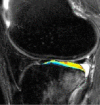

Purpose: To longitudinally evaluate cartilage matrix changes by using magnetic resonance (MR) imaging T1(ρ) (T1 relaxation time in rotating frame) and T2 quantification and to study the relationship between meniscal damage and cartilage degeneration in anterior cruciate ligament (ACL)-reconstructed knees.

Materials and methods: This was an institutional review board-approved, HIPAA-compliant study. Informed consent was obtained. Twelve patients with acute ACL injuries were imaged with 3.0-T MR imaging at baseline (after injury and prior to ACL reconstruction) and 1 year after ACL reconstruction. Ten age-matched healthy subjects were studied as controls. Cartilage T1(ρ) and T2 were quantified in full thickness, superficial, and deep layers of defined subcompartments at baseline and follow-up in ACL-injured knees and were compared with measures acquired in matched regions of control knees. Meniscal lesions were graded by using modified subscores of the Whole-Organ Magnetic Resonance Imaging Score system.

Results: T1(ρ) values of the posterolateral tibial cartilage in ACL-injured knees were significantly elevated at baseline compared with T1(ρ)values of control knees and were not fully recovered at 1-year follow-up. T1(ρ) values of weight-bearing medial femorotibial cartilage in ACL-injured knees were significantly elevated at 1-year follow-up compared with those of control knees. No significant differences in T2 values between ACL-injured and control knees were found. Patients with lesions in the posterior horn of the medial meniscus showed a greater increase of T1(ρ) and T2 from baseline to follow-up in adjacent cartilage than patients without lesions in the medial meniscus.

Conclusion: Quantitative MR imaging T1(ρ) and T2 enable detection of changes in the cartilage matrix of ACL-reconstructed knees as early as 1 year after ACL reconstruction.